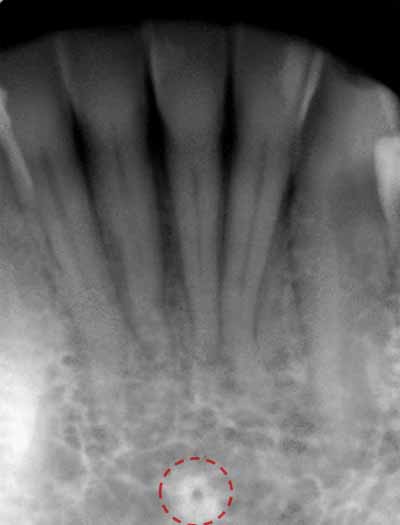

下顎の舌側表面の中央には骨の突起であるオトガイ棘があり、この骨の突起は口底の筋肉の付着部として機能します。オトガイ棘は、下顎の中切歯の下にある丸いまたはリング状のエックス線不透過構造として、X線写真上に描かれます。オトガイ棘と同じ領域の中央には舌孔があり、1つまたは複数の小さな丸いエックス線透過性の点として描かれています (画像17aおよび17bを参照)。